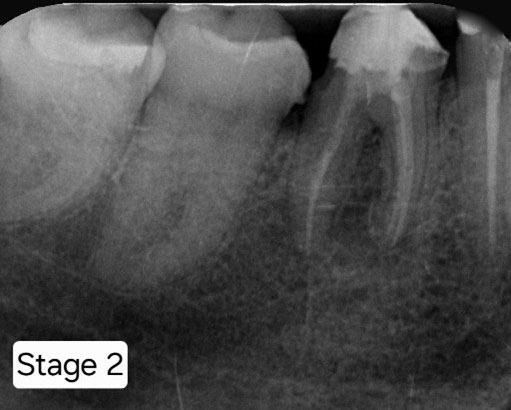

Case Study 2

Pathology present in the Lower Left 7 – the patient was motivated to save the tooth.

RCT completed with posts placed.

Follow up x-ray taken after 6 months.